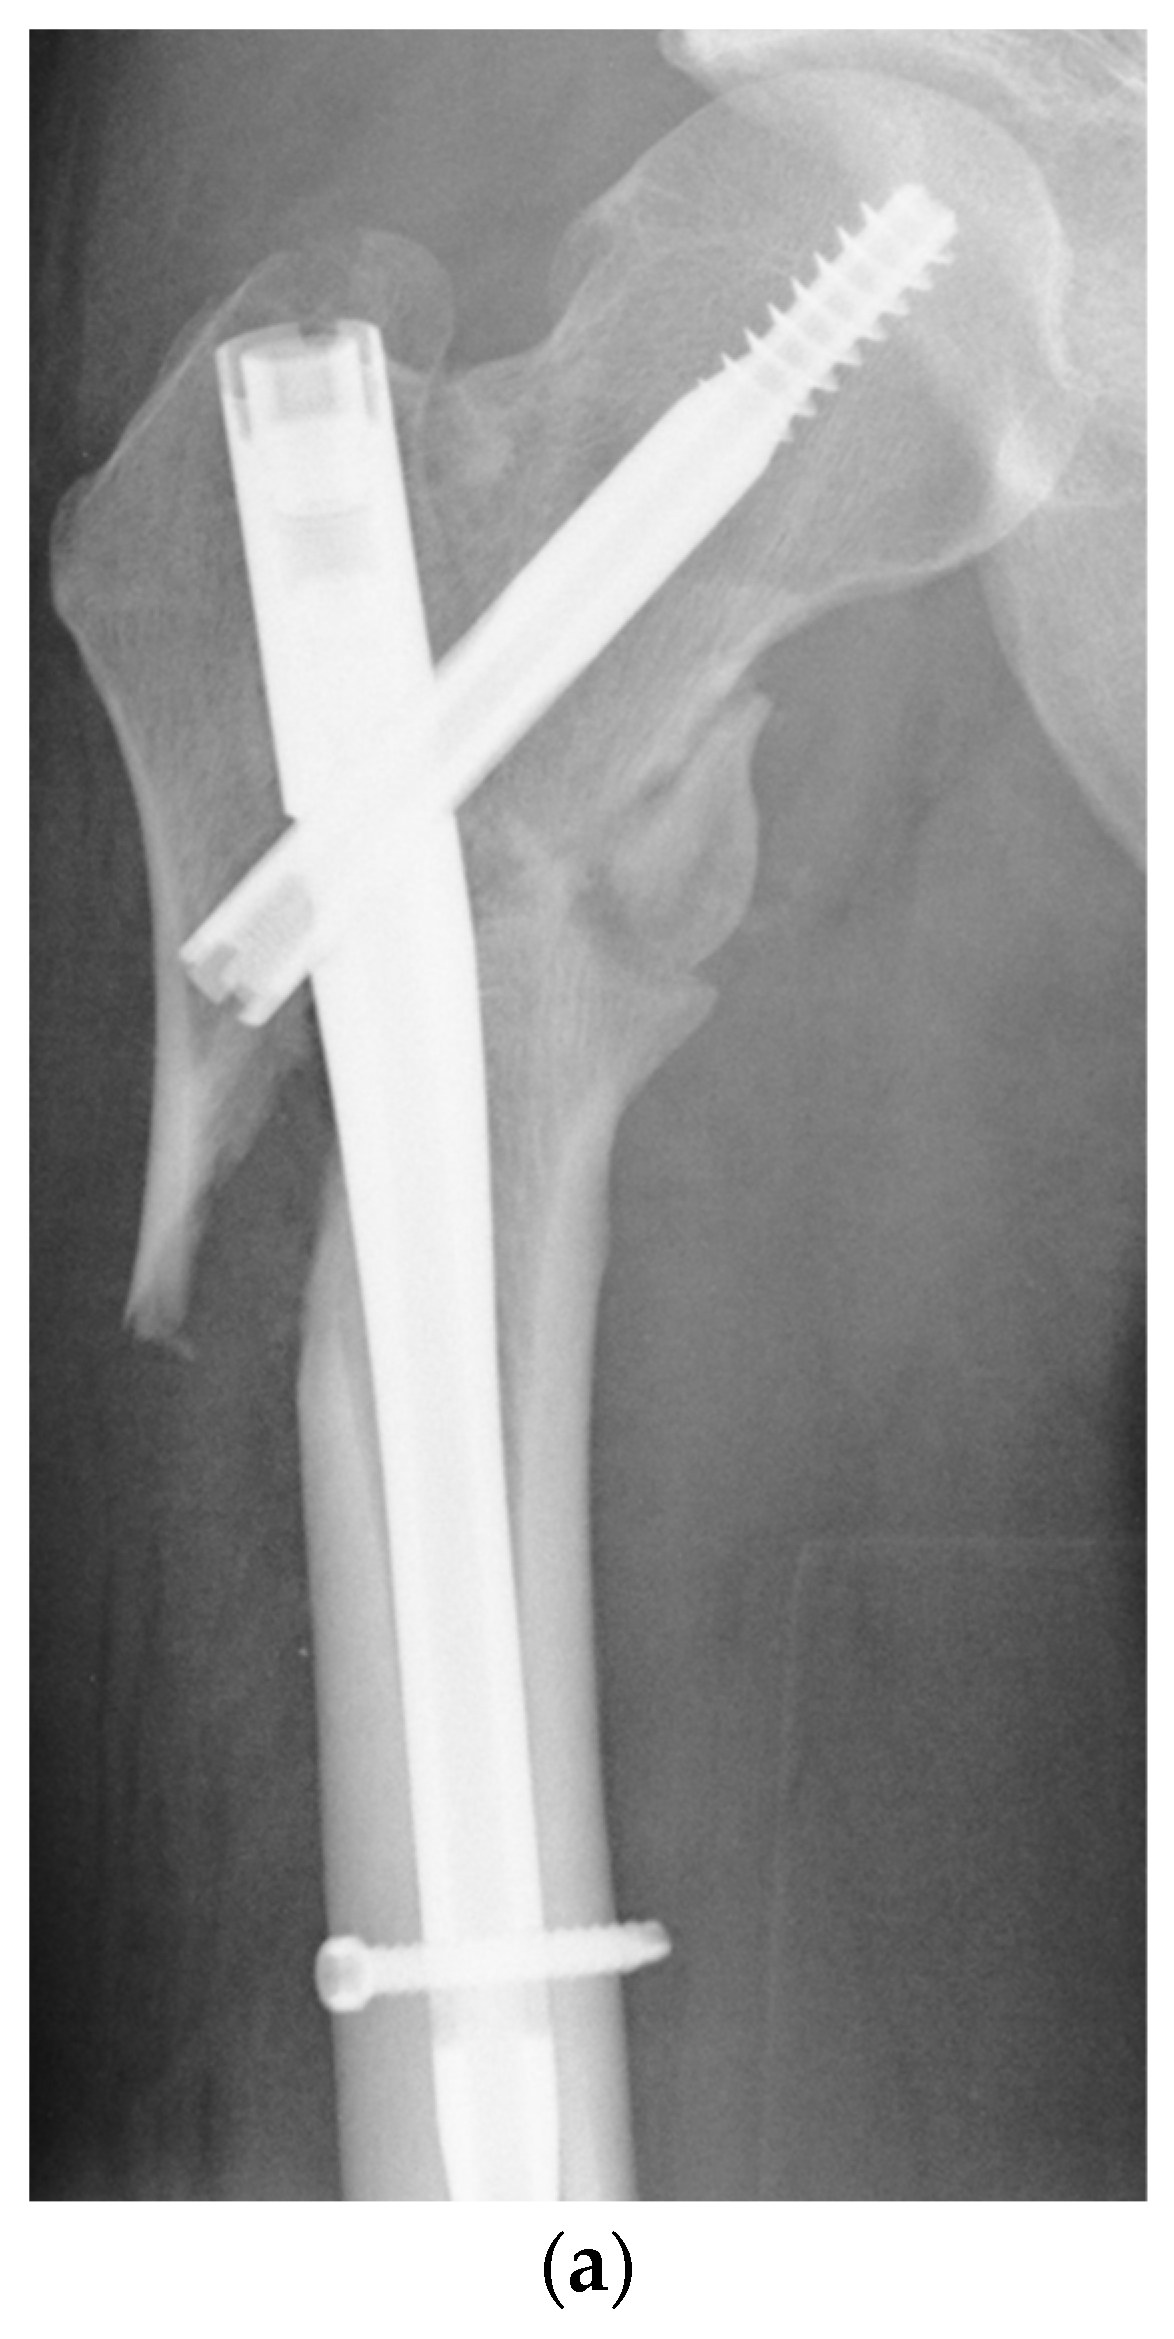

Functional and Radiological Results Following Revision Blade Plating and Cephalomedullary Nailing in Aseptic Trochanteric and Subtrochanteric Nonunion

2.2. Surgical Procedures